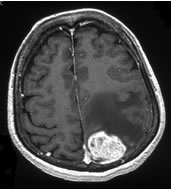

転移性脳腫瘍

近年、ガンマナイフ症例数のほぼ半分を占めています。基本的には1〜10病変未満が良い適応となります。複数の病変であっても、1回の治療ですべてを治療することが可能です。

![]() ![]() |

| ガンマナイフ時 |

| 6ヶ月後 |